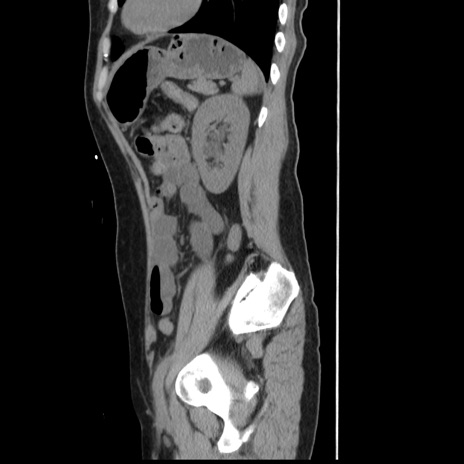

症例10(矢状断像)

【症例】 50歳代女性

【主訴】 腹痛

【現病歴】前日生レバーを食べた。今朝に排便あり。 昼前に突然発症の腹痛を生じ、当院救急外来を受診した。

【既往歴】 子宮筋腫にてで子宮全摘後

【身体所見】 意識清明、腹部:平坦、軟、下腹部やや左を中心に圧痛・反跳痛あり、筋性防御あり

【データ】WBC 7800、CRP 0.07